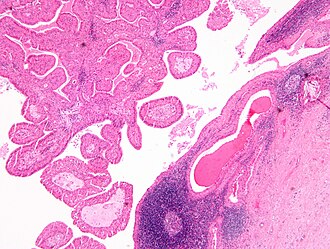

Warthin tumour. H&E stain.

LM papillae with a two rows of pink (eosinophilic) epithelial cells (with cuboidal basal cells and columnar luminal cells), fibrous capsule, cystic space filled with debris, lymphoid stroma

• Papillae (nipple-shaped structures) with a two rows of pink (eosinophilic) epithelial cells (with cuboidal basal cells and columnar luminal cells) - key feature.

• Fibrous capsule - pink & homogenous on H&E stain.

• Cystic space filled with debris in situ (not necrosis).

• Lymphoid stroma.

The sections show a cystic tumour with lymphoid tissue associated with benign salivary gland tissue. The lymphoid tissue is composed of small cells and forms morphologically unremarkable follicles. The cyst-lining epithelium has a bilayered appearance and is composed of cells with abundant eosinophilic cytoplasm and nucleoli. The tumour focally extends to the edge of the tissue (ink present on tumour).